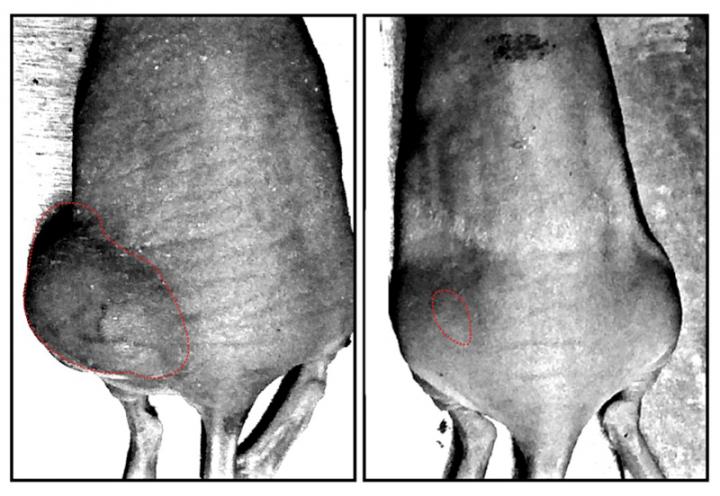

The left and right show xenograft tumors of parental cells and PTPRZ knockdown cells, respectively.